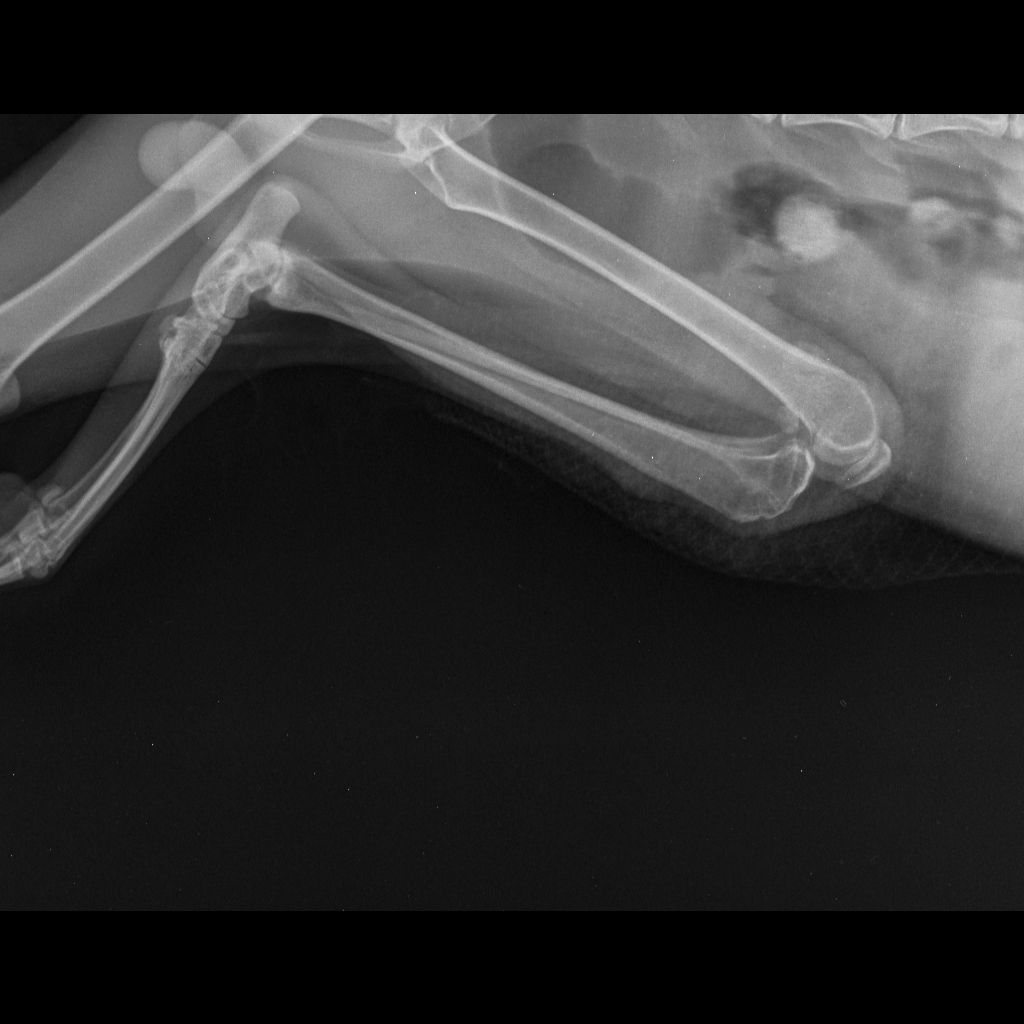

| История болезней/травм | 28.12.2025 - скальп кожи с бедра левой лапы и укол в колено. Где-то зацепился и потянул. Месяц так проходил, никто не помогал. Благодаря морозу заражения сильного не было. Обращение в ветклинику "КОТоПЁС": осмотр, стрижка, чистка раны солевым раствором, наложение повязки с лекарством (септо-спрей, бранолинд) и антибиотики (Кладакса, Марфлоксин) с обезболивающим, рентген. 29.12.2025 - Обращение в ветклинику "КОТоПЁС": осмотр, чистка раны солевым раствором, наложение повязки с лекарством (септо-спрей, бранолинд) и антибиотики с обезболивающим. 30.12.2026 - антибиотики. 31.12.2025 - Обращение в ветклинику "Эмили": чистка раны солевым раствором, наложение повязки с лекарством (септо-спрей, бранолинд) и антибиотики. 01.01.2026 - антибиотики. 02.01.2026 - чистка раны солевым раствором, наложение повязки с лекарством (септо-спрей, бранолинд) и антибиотики. 03.01.2026 - антибиотики. 04.01.2026 - Обращение в ветклинику "КОТоПЁС": осмотр, чистка раны солевым раствором, наложение повязки с лекарством (септо-спрей, бранолинд) и антибиотики, рентген. 05.01.2026 - антибиотики. 06.01.2026 - чистка раны солевым раствором, наложение повязки с лекарством (септо-спрей, бранолинд) и антибиотики. 07.01.2026 - антибиотики. 08.01.2026 - чистка раны солевым раствором, наложение повязки с лекарством (септо-спрей, бранолинд) и антибиотики. 10.01.2026 - Обращение в ветклинику "КОТоПЁС": осмотр, чистка раны солевым раствором, наложение повязки с лекарством (септо-спрей, бранолинд) и антибиотики. 11.01.2026 - антибиотики, глистогонка. 12.01.2026 - чистка раны солевым раствором, наложение повязки с лекарством (септо-спрей, бранолинд) и антибиотики. 13.01.2026 - чистка раны солевым раствором, наложение повязки с лекарством (септо-спрей, бранолинд) и антибиотики. 14.01.2026 - антибиотики. 15.01.2026 - антибиотики. 16.01.2026 - чистка раны солевым раствором, наложение повязки с лекарством (септо-спрей, бранолинд) и антибиотики. 17.01.2026 - антибиотики. 18.01.2026 - антибиотики. 19.01.2026 - чистка раны солевым раствором, наложение повязки с лекарством (септо-спрей, бранолинд) и антибиотики. 20.01.2026 - чистка раны солевым раствором, наложение повязки с лекарством (септо-спрей, Повязка мазевая Исполнение-Д4 50х70) и антибиотики. 23.01.2026 - чистка раны солевым раствором, наложение повязки с лекарством (септо-спрей, Повязка мазевая Исполнение-Д4 50х70). 26.01.2026 - чистка раны солевым раствором, наложение повязки с лекарством (септо-спрей, Повязка мазевая Исполнение-Д4 50х70). 29.01.2026 - чистка раны солевым раствором, наложение повязки с лекарством (септо-спрей, Повязка мазевая Исполнение-Д4 50х70) и антибиотики. 30.01.2026 - антибиотики. 31.01.2026 - чистка раны солевым раствором, наложение повязки с лекарством (септо-спрей, бранолинд) и антибиотики. 01.02.2026 - антибиотики. 02.02.2026 - чистка раны солевым раствором, наложение повязки с лекарством (септо-спрей, бранолинд) и антибиотики. 03.02.2026 - чистка раны солевым раствором, наложение повязки с лекарством (септо-спрей, бранолинд). 04.02.2026 - чистка раны солевым раствором, наложение повязки с лекарством (септо-спрей, бранолинд). 06.02.2026 - чистка раны солевым раствором, наложение повязки с лекарством (септо-спрей, ихтиоловая мазь). 07.02.2026 - чистка раны солевым раствором, наложение повязки с лекарством (септо-спрей, бранолинд). 09.02.2026 - чистка раны солевым раствором, наложение повязки с лекарством (септо-спрей, бранолинд). 11.02.2026 - чистка раны солевым раствором, наложение повязки с лекарством (септо-спрей, бранолинд). 12.02.2026 - чистка раны солевым раствором, наложение повязки с лекарством (септо-спрей, бранолинд). 14.02.2026 - чистка раны солевым раствором, наложение повязки с лекарством (септо-спрей, бранолинд). 15.02.2026 - чистка раны солевым раствором, наложение повязки с лекарством (септо-спрей, Повязка мазевая Исполнение-Д4 50х70). 17.02.2026 - чистка раны солевым раствором, наложение повязки с лекарством (септо-спрей, Повязка мазевая Исполнение-Д4 50х70). 19.02.2026 - чистка раны солевым раствором, наложение повязки с лекарством (септо-спрей, Повязка мазевая Исполнение-Д4 50х70). 20.02.2026 - чистка раны солевым раствором, наложение повязки с лекарством (септо-спрей, ихтиоловая мазь). 22.02.2026 - чистка раны солевым раствором, наложение повязки с лекарством (септо-спрей, ихтиоловая мазь). 24.02.2026 - чистка раны солевым раствором, наложение повязки с лекарством (септо-спрей, ихтиоловая мазь). 26.02.2026 - чистка раны солевым раствором, наложение повязки с лекарством (септо-спрей, ихтиоловая мазь). 28.02.2026 - чистка раны солевым раствором, наложение повязки с лекарством (септо-спрей, ихтиоловая мазь). 02.03.2026 - чистка раны солевым раствором, наложение повязки с лекарством (септо-спрей, ихтиоловая мазь). 03.03.2026 - чистка раны солевым раствором, наложение повязки с лекарством (септо-спрей, ихтиоловая мазь). 04.03.2026 - чистка раны солевым раствором, наложение повязки с лекарством (септо-спрей, ихтиоловая мазь). 06.03.2026 - чистка раны солевым раствором, наложение повязки с лекарством (септо-спрей, ихтиоловая мазь). 07.03.2026 - чистка раны солевым раствором, наложение повязки с лекарством (септо-спрей, ихтиоловая мазь). 08.03.2026 - чистка раны солевым раствором, наложение повязки с лекарством (септо-спрей, ихтиоловая мазь). 10.03.2026 - чистка раны солевым раствором, наложение повязки с лекарством (септо-спрей, ихтиоловая мазь). 12.03.2026 - чистка раны солевым раствором, наложение повязки с лекарством (септо-спрей, ихтиоловая мазь). 14.03.2026 - чистка раны солевым раствором, наложение повязки с лекарством (йод и солевой раствор, ихтиоловая мазь). 16.03.2026 - чистка раны солевым раствором, наложение повязки с лекарством (йод и солевой раствор, ихтиоловая мазь) и антибиотики. 17.03.2026 - антибиотики. 18.03.2026 - чистка раны солевым раствором, наложение повязки с лекарством (йод и солевой раствор, ихтиоловая мазь) и антибиотики. 19.03.2026 - глистогонка "Дирофен". 20.03.2026 - чистка раны солевым раствором, наложение повязки с лекарством (йод и солевой раствор, ихтиоловая мазь) и антибиотики. 22.03.2026 - чистка раны солевым раствором, наложение повязки с лекарством (йод и солевой раствор, ихтиоловая мазь). 24.03.2026 - чистка раны солевым раствором, наложение повязки с лекарством (йод и солевой раствор, ихтиоловая мазь). 26.03.2026 - чистка раны солевым раствором, наложение повязки с лекарством (йод и солевой раствор, Повязка мазевая Исполнение-Д4 50х70) и антибиотики. 27.03.2026 - антибиотики. 28.03.2026 - чистка раны солевым раствором, наложение повязки с лекарством (йод и солевой раствор, Повязка мазевая Исполнение-Д4 50х70) и антибиотики. 29.03.2026 - антибиотик 30.03.2026 - чистка раны солевым раствором, наложение повязки с лекарством (йод и солевой раствор, Повязка мазевая Исполнение-Д4 50х70) и антибиотики. 31.03.2026 - антибиотик 01.04.2026 - чистка раны солевым раствором, наложение повязки с лекарством (йод и солевой раствор, Повязка мазевая Исполнение-Д4 50х70). 04.04.2026 - чистка раны солевым раствором, наложение повязки с лекарством (йод и солевой раствор, ихтиоловая мазь). 06.04.2026 - чистка раны солевым раствором, наложение повязки с лекарством (йод и солевой раствор, Повязка мазевая Исполнение-Д4 50х70). 08.04.2026 - чистка раны солевым раствором, наложение повязки с лекарством (йод и солевой раствор, Повязка мазевая Исполнение-Д4 50х70). 10.04.2026 - чистка раны солевым раствором, наложение повязки с лекарством (йод и солевой раствор, Повязка мазевая Исполнение-Д4 50х70). 12.04.2026 - чистка раны солевым раствором, наложение повязки с лекарством (йод и солевой раствор, Повязка мазевая Исполнение-Д4 50х70). 14.04.2026 - чистка раны солевым раствором, наложение повязки с лекарством (йод и солевой раствор, Повязка мазевая Исполнение-Д4 50х70), глистогонка "Дирофен" и антибиотик (Кладакса). Заметно перестаёт кушать. 15.04.2026 - антибиотик (Кладакса). Плохо ест сам. 16.04.2026 - чистка раны солевым раствором, наложение повязки с лекарством (йод и солевой раствор, Повязка мазевая Исполнение-Д4 50х70) и антибиотик (Кладакса). 17.04.2026 - антибиотик (Кладакса). Ест только рыбку. 18.04.2026 - чистка раны солевым раствором, наложение повязки с лекарством (йод и солевой раствор, Повязка мазевая Исполнение-Д4 50х70) и антибиотик (Кладакса). 20.04.2026 - чистка раны солевым раствором, наложение повязки с лекарством (йод и солевой раствор, Повязка мазевая Исполнение-Д4 50х70). Принудительное кормление паштетом, пьёт сам. 22.04.2026 - чистка раны солевым раствором, наложение повязки с лекарством (йод и солевой раствор, Повязка мазевая Исполнение-Д4 50х70). Принудительное кормление паштетом, пьёт сам. 24.04.2026 - чистка раны солевым раствором, наложение повязки с лекарством (йод и солевой раствор, Повязка мазевая Исполнение-Д4 50х70). Принудительное кормление паштетом, пьёт сам. 26.04.2026 - чистка раны солевым раствором, наложение повязки с лекарством (мазь стрептоцид и солевой раствор, Повязка мазевая Исполнение-Д4 50х70). Принудительное кормление паштетом и водой. 28.04.2026 - чистка раны солевым раствором, наложение повязки с лекарством (мазь стрептоцид и солевой раствор, Повязка мазевая Исполнение-Д4 50х70). Принудительное кормление паштетом и водой. 30.04.2026 - чистка раны солевым раствором, наложение повязки с лекарством (йод и солевой раствор, ихтиоловая мазь). Принудительное кормление паштетом и водой. Обращение в ветклинику "ЭМИЛИ". 01.05.2026 - Обращение в ветклинику "ЭМИЛИ" - диагноз ФИП, откачка 300 мл жидкости из брюшной полости. Капельница и приём Коронакэт. 02.05.2026 - смерть. |